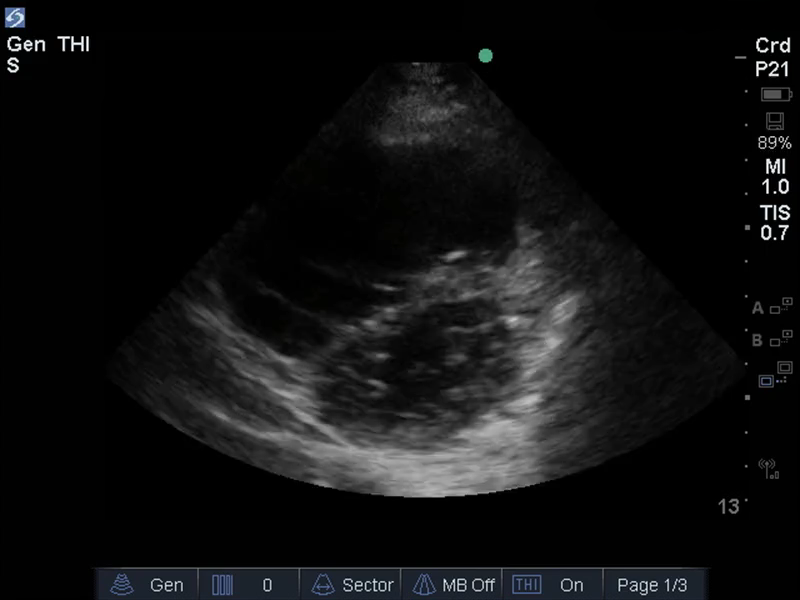

TEE心臓RVサイズ機能の画像